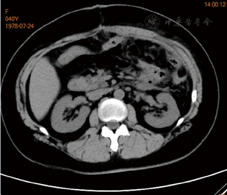

术后仁济医院放疗23次,放疗剂量46 Gy分23次。定期我院随访,2018年4月18日复查CA125为48.54 U/ml,略高于正常;8月15日复查CA125为24.65 U/ml。2019年6月自觉左上腹隐痛,于6月27日行腹部增强MRI,提示胃、胰尾及脾间隙内见一大小约103.5 mm×78.0 mm软组织占位,间皮瘤可能,横结肠系膜、大网膜多发小节结影,种植改变?腹膜后淋巴结增大(图1,图2,图3)。